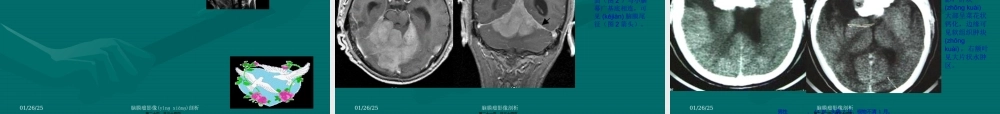

脑膜瘤脑膜瘤CTCT、、MRIMRI表表现现(biǎoxiàn)(biǎoxiàn)第一页,共三十四页。01/26/25脑膜瘤影像(yǐnɡxiànɡ)剖析(pínɡshù)•脑膜瘤起源于蛛网膜细胞丛,与蛛网膜颗粒关系密切,是典型的脑外肿瘤。多见于中年人,女性多于男性,好发于矢状窦旁,大脑凸面,蝶骨嵴,嗅沟,桥小脑(xiǎonǎo)角,大脑镰或天幕。少数发生于脑室内,多为单发。脑膜瘤常见的病理类型包括:⑴内皮型:肿瘤有蛛网膜上皮细胞组成,是最常见的类型。⑵纤维型:由纤维母细胞和胶原纤维组成。⑶血管瘤型:瘤内有丰富的血管成分。⑷砂粒型:瘤内含有大量砂粒体。⑸混合型:也较多见,瘤内含有上述四种成分。⑹恶性脑膜瘤:细胞形态及生长特征具有恶性肿瘤的特点,且可以发生转移。第二页,共三十四页。01/26/25脑膜瘤影像剖析(biǎoxiàn)•(一)常表现为边界清楚的肿块,以宽基底与颅骨内板或硬脑膜相贴。(如病变中心(zhōngxīn)发生于额顶上部,由于CT横断面扫描的局限性,部分病变似脑内占位,CT冠状面、矢状面重建及MRI有助于显示病变特征。)平扫右侧额叶见等密度肿块,外侧(wàicè)与颅板相贴,周围见大片水肿,占位效应明显。增强后明显均匀强化,CT值上升约110Hu。第三页,共三十四页。01/26/25脑膜瘤影像(yǐnɡxiànɡ)剖析•(二)平扫常为均一略高或高密度肿块,钙化常见,常为细小点状、沙粒状或不规则,罕见整个瘤体钙化(见下图)。增强扫描呈均一明显强化。边界清楚锐利。少数病例还可显示肿瘤(zhǒngliú)周边有一薄层环状强化影(见下图),可能是肿瘤(zhǒngliú)包膜所含血管较丰富和包绕肿瘤(zhǒngliú)的静脉或引流静脉较多所致。CTCT表现表现(biǎoxiàn)(biǎoxiàn)第四页,共三十四页。01/26/25脑膜瘤影像剖析(shǎojiàn)•女性(nǚxìng),55岁,头昏、头痛2年,加重一月。CTCT表现表现(biǎoxiàn)(biǎoxiàn)第五页,共三十四页。01/26/25脑膜瘤影像(yǐnɡxiànɡ)剖析诊断依据:1、病变呈类圆形,实性部分明显强化,内侧低密度坏死区内见液液平面,密度下高上低,考虑为瘤内出血所致;2、病灶外缘与脑膜(nǎomó)呈广基相贴,骨窗示相连的颅骨骨质较对侧更厚,且内板边缘明显,较毛躁而不光整锐利;3、占位性病变周围右侧额叶脑实质见低密度水肿带,脑室及中线结构移位。病理诊断:右侧额叶镰旁“囊性脑膜瘤伴瘤内出血”鉴别诊断:主要和胶质瘤进行鉴别,胶质瘤的总体强化程度不如脑膜瘤,其病灶密度较低且常不均匀。第六页,...